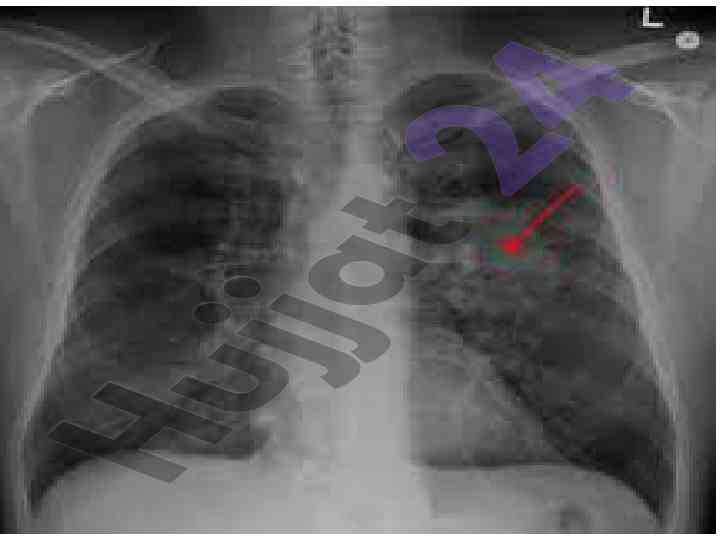

Oʻpka va koks oraligʻi kasalliklari nur bilan tekshirish

Oʻpka kasalliklarini rentgenologik jihatdan tekshirish usullari va ularning belgilari haqida ilmiy maqola. Oʻpka maydonining qorayishi va patologiyalari haqida ma'lumotlar.